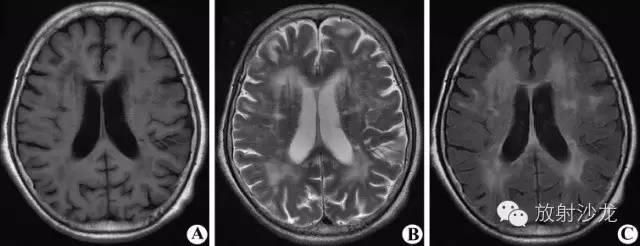

MRI平扫示双侧侧脑室稍扩大,双侧额叶深部及放射冠区可见斑片状异常信号区,T2WI(A、B)及水抑制序列(C、D)呈高信号;双侧基底节及右侧放射区可见多灶腔隙性梗塞灶,呈长T2改变。

双侧侧脑室周围及放射冠区对称性月晕状信号异常。T1WI(A)呈稍低信号,T2WI(B)及FLAIR(C)呈稍高信号,占位效应不明显。围绕侧脑室呈大片状,其边缘多模糊不清,可伴有脑深部腔隙软化灶,无占位效应,增强扫描无强化。